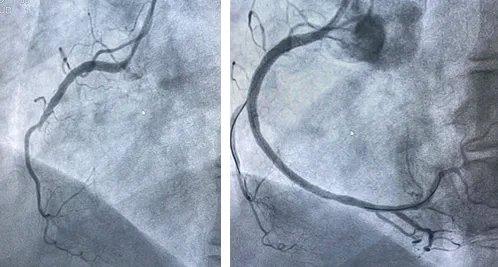

“气死我了!”夫妻旅游,在咖啡馆因行程安排大吵一架,51岁妻子气到胸痛紧急送医,确诊为急性心肌梗死,情况十分危急……医生迅速对这位51岁的妻子展开了全力救治。经过一系列检查,发现她本身就存在一定的心血管基础问题,而这次激烈的争吵和情绪的巨大波动成为了诱发急性心肌梗死的导火索。 在手术室外,丈夫满脸懊悔,不停地自责:“都怪我,非要在那时候争论行程,要是我让着她一点,也不会弄成这样啊。”他心急如焚,在走廊上来回踱步,眼神中满是担忧和愧疚。 经过数小时的紧张手术,医生终于从手术室走了出来,告诉丈夫手术很成功,但患者还需要在重症监护室观察一段时间。丈夫悬着的心这才稍稍放下,他默默发誓,以后一定要好好照顾妻子,不再让她生气。 这件事也给其他夫妻敲响了警钟。旅游本是为了放松心情、增进感情,却因为一点行程安排的分歧差点酿成大祸。在生活中,夫妻之间难免会有争吵和分歧,但一定要学会控制情绪,保持冷静,尤其是对于有基础疾病的人来说,情绪的剧烈波动可能会带来意想不到的严重后果。希望大家都能从这个事件中吸取教训,珍惜身边人,用平和的心态去面对生活中的大小事。